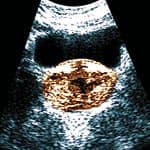

The acronym PSA stands for prostate-specific antigen, the most abundant protein synthesized in the prostate gland. Men have their blood tested for PSA in order to detect prostate cancer at an early stage when it is often curable. The PSA test can also help assess the efficacy of various prostate cancer treatments. Until now, PSA has been viewed only as a blood indicator of prostate cancer, infection, or inflammation. Emerging evidence, however, reveals that PSA may be more than just a marker of prostate health. It appears that PSA itself may play a role in the progression and metastasis of prostate cancer,1-3 thus opening up new therapeutic pathways for preventing and treating this epidemic disease. A significant amount of published data associates high intake of certain nutrients with reduced incidences of prostate cancer.4-12 A few studies suggest that these same nutrients may even help control advanced stages of the disease.13,14 Scientists are now finding that some of these nutrients function to reduce or interfere with PSA activity in the prostate gland. With new data suggesting that PSA itself may be involved in the progression and spread of prostate cancer, the anti-PSA activity of these nutrients becomes significant and helps explain why men who consume certain nutrients have lower incidences of the disease and a slower progression of disease when prostate cancer has been diagnosed. Staggering Statistics on Prostate CancerCells in the prostate gland are very prone to gene mutation, while other tissues in the same anatomical region, such as the seminal vesicles, develop primary cancers at a significantly lower rate.15 Autopsy evidence indicates that prostate cancer is histologically evident in up to 34% of men aged 40-49 and up to 70% of men aged 80 and older.16,17 Most men, however, never progress to clinically diagnosed disease, indicating the presence of control mechanisms that keep prostate cancer cell colonies small and thus controlled. It now appears possible to partially regulate some of the genes that ordinarily enable cells to divide out of control and eventually form a prostate tumor, which may then proliferate, invade, and metastasize. These new findings make it more important than ever for men to monitor their blood PSA levels to detect prostate cancer at its earliest stages.

Curcumin Induces Cancer Cell SuicideCancer cells do not follow normal, healthy cell suicide programs. Old cells need to die and be discarded, but cancer cells proliferate and grow. Numerous studies over the past two years have identified specific mechanisms by which curcumin inhibits the growth of prostate cancer cells and then activates genes that tell cancer cells to self-destruct (also referred to as apoptosis).41,42 One study showed that curcumin reprograms prostate cancer cells so as to make them less likely to metastasize to the bone, while another study demonstrated that curcumin has radiation-sensitizing effects, making cancer cells more vulnerable to destruction by conventional radiation therapy.43,44 The research on curcumin is so promising that pharmaceutical companies are currently developing curcumin analogs that can be patented as anti-cancer therapies.45,46 Critical Importance of Annual PSA TestingIn 2004, the New England Journal of Medicine published an article indicating that the rate of increase in PSA is a more important predictor of mortality than the PSA reading itself. Men who showed a 2.0 ng/ml or greater increase in PSA from the previous year’s level were 10 times more likely to die within seven years.47 The researchers recommended that men over the age of 35 should have a baseline PSA reading and then retest each year to measure the rate of increase (PSA velocity). A sharp rise in PSA mandates the need for more comprehensive evaluation and treatment. Without previous PSA readings, it is impossible for your doctor to calculate PSA velocity. Optimal measurement of PSA velocity requires at least three PSA readings, with each obtained at least six months apart and tested at the same laboratory using the same PSA laboratory procedure. In summary, accumulating data suggest that PSA is no longer merely a laboratory test of prostate gland activity. Instead, PSA is recognized as a functional protein: an enzyme that may facilitate prostate cancer cell proliferation, invasion, and metastasis. Taking steps to suppress PSA may reduce prostate cancer risk and progression. Meaningful reductions in PSA, as demonstrated in many of the studies cited in this article, appear achievable by using natural supplements like lycopene, soy, green tea, and boron, as well as through prescription drugs such as Avodart® or Proscar®, which normally reduce serum PSA levels by 40-50%.48-50